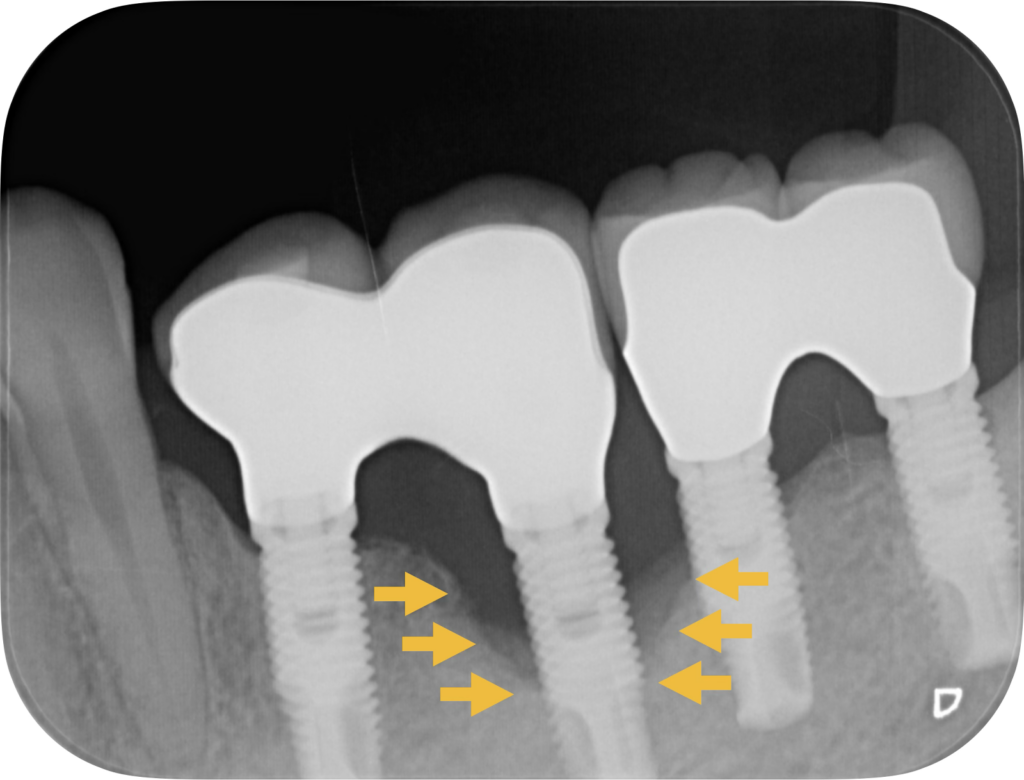

図:インプラント周囲炎により溶けてしまった骨(黄矢印)

インプラントの「歯周病」のようなものを、専門的には インプラント周囲炎 と呼びます。これは、プラークが溜まることで細菌が増殖し、炎症が進行して骨が減少することを指します。進行が進むと骨がインプラントを支えられなくなり、最悪の場合インプラントが動揺・脱落するリスクがあります。

しかも、この状態は初期に自覚症状が出にくく、気付いた時にはかなり進行しているケースもあります。だからこそ、定期検診での早期発見・対応が重要なのです。